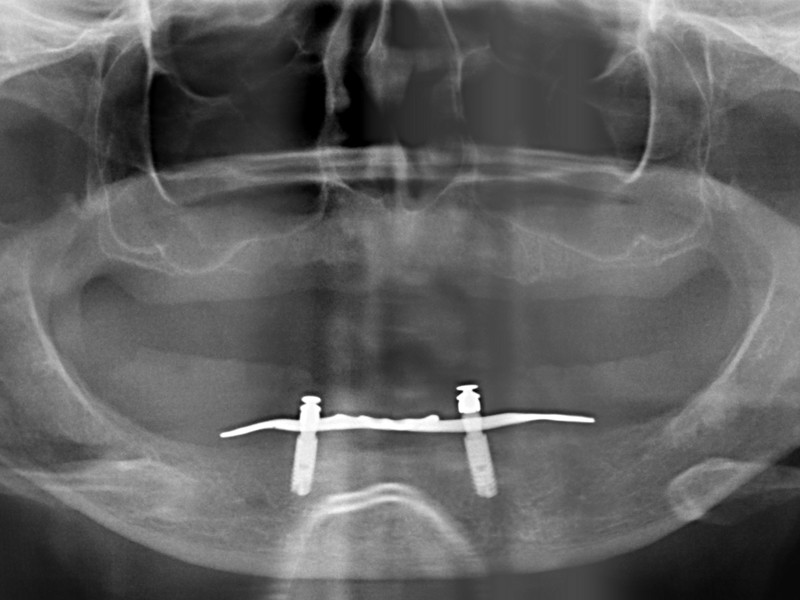

Subperiosteálny implantát je vytvorený presne na mieru . Nalieha priamo na povrch kosti a je väčšinou fixovaný mikroskrutkami. Do ústnej dutiny zasahujú len retenčné prvky pre uchytenie hybridnej snímateĺnej náhrady. Môže byť použitý v maxille aj mandibule.

Postup výroby spočíva v CT scane kosti, analýze, digitálnej výrobe 3D modelu kosti, individuálnom nadizajnovaní optimálneho tvaru subperiosteálneho implantátu, ktorý je vyrobený výhradne z bioinertného titánu najvyššej kvality grade 5. Finálny produkt je po povrchovej úprave inzerovaný operačne v lokálnej alebo celkovej anestéze. Pooperačné hojenie sliznice vyžaduje krátky čas ktorý využívame na zhotovenie hybridnej snímateĺnej náhrady podĺa náročnosti pacienta.